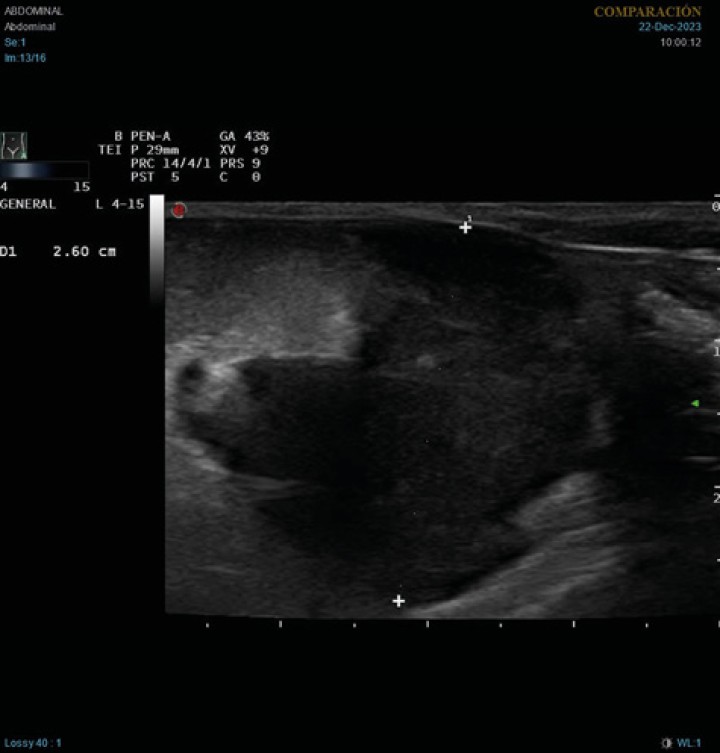

En la ecografía abdominal se observó esplenomegalia con parénquima heterogéneo, linfadenopatía abdominal generalizada y una masa hipoecoica de 2,6 cm de diámetro en la zona de proyección de los linfonodos mesentéricos (Fig. 1). También se observaron hallazgos ecográficos compatibles con peritonitis, como aumento de la ecogenicidad difusa del peritoneo y presencia de líquido libre anecoico, en este caso no puncionable. Por cuestiones económicas los tutores rechazaron ampliar los análisis sanguíneos con un proteinograma.

Imagen ecográfica longitudinal del abdomen caudal. Masa heterogénea, principalmente hipoecoica, de 2,6 cm de diámetro, con hiperecogenicidad de la grasa adyacente.